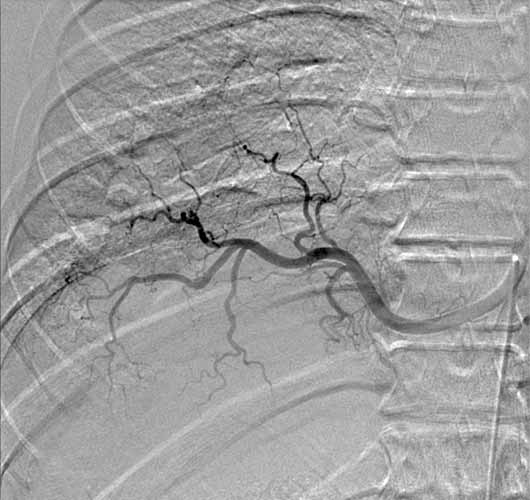

A previously healthy 43-year-old male presented with cough, fevers, and leukocytosis. A chest radiograph (Figure 1) revealed extensive consolidation in the right lower lung containing multiple cavities with air-fluid levels consistent with a necrotizing infection. A chest computed tomogram (Figure 2) showed an abscess cavity and consolidation in the right lower lobe with an aberrant blood supply from the descending aorta. This systemic blood supply was confirmed by subsequent 3D reconstruction (Figure 3). He was initially treated with IV antibiotics, resulting in normalization of his temperature and white blood cell count. He was then discharged home on a 3-week course of oral antibiotics. Three days prior to a planned surgical resection, he underwent angiographic localization of the feeding artery (Figure 4) and coil embolization (Figure 5).

To prevent complications from infection, hemorrhage, and possible malignancy, surgical resection of ILS is recommended [7]. Preoperative coil embolization of the arterial supply can decrease the risk of hemorrhagic complications and has been reported in the pediatric literature as an alternative to surgery [8]. However, intraoperative vascular control of this vessel may be more difficult if the coils are positioned in the artery outside of the sequestration rather than within the sequestration. Operative approaches involving thoracoscopy and thoracotomy have been reported, utilizing lobectomy, sequestrectomy, and wedge resection [9]. A recent review found pediatric and adult ILS anatomy, presentation, and treatment options to be similar [10].